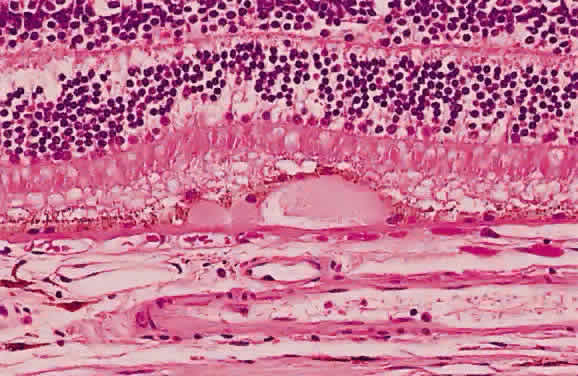

Pigment epithelial melanin may accumulate within the retina, especially around retinal vessels (Fig. 50). Because the small retinal vessels branch frequently, the pigment appears to have the “bone-corpuscular” appearance typically seen in retinitis pigmentosa (Fig. 51) but also after blunt ocular trauma and intraocular inflammation.

Fig. 50. Photomicrograph of primary retinitis pigmentosa demonstrating pigment accumulation surrounding a superficial blood vessel and absence of the rods and cones in the posterior retinal layers. (Courtesy of Ralph C. Eagle Jr, MD, Philadelphia, PA)

Fig. 51. A. Fundus photograph of retinitis pigmentosa with bone spicule pigmentation. The “bone-corpuscular” appearance is the result of pigment epithelial melanin accumulation around the small retinal vessel branches. B. Advanced retinitis pigmentosa. There is marked pigment clumping along with waxy pallor of the disc and attenuated arterioles.